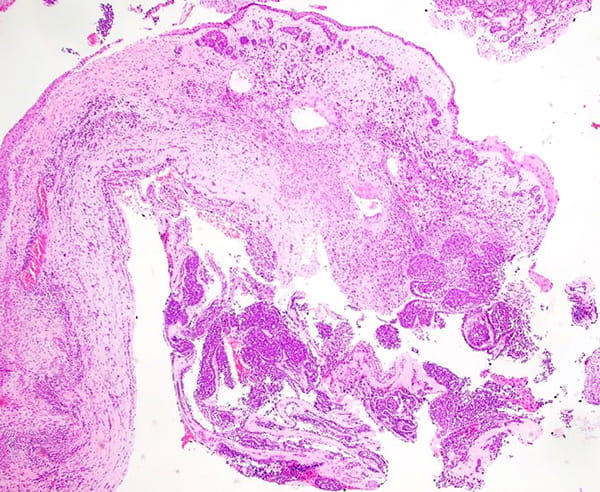

A 53-year-old female with no history of malignancy presented with a two-month history of nasal congestion. CT imaging revealed a 3.8 cm soft tissue mass in the right nasal cavity, extending into the frontal sinus and nasopharynx. One of the differential diagnoses based on radiologic findings is a sinonasal polyp.

The specimen, obtained from a nasal cavity biopsy, consists of multiple tissue fragments measuring between 0.5 cm and 1.5 cm.

The tumor predominantly grows in the submucosal areas, forming cribriform nests, ductal structures, trabecular arrangements, or solid sheets. The tumor cells are basaloid with scant cytoplasm. Focal areas of squamous differentiation, characterized by eosinophilic cytoplasm, are observed. The overlying squamous mucosa exhibits high-grade dysplasia.